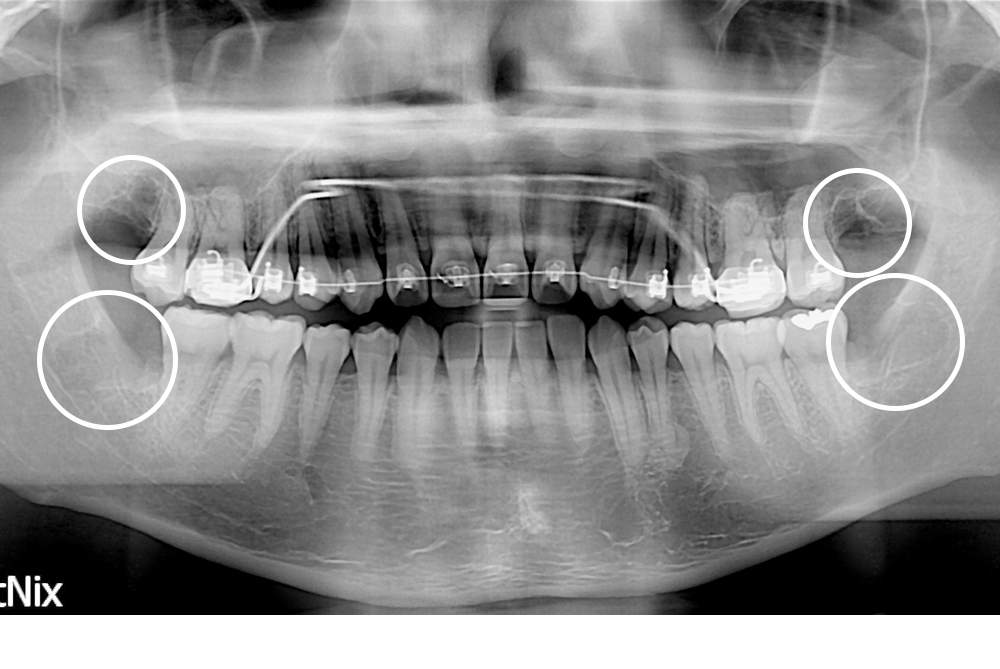

[사랑니] 매복 사랑니 발치

치료전 : 2016-02-10